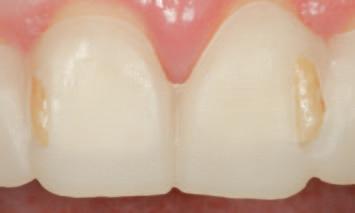

Digitally guided tooth reduction in the contemporary management of amelogenesis imperfecta

Balancing biological cost with the demand for restorative space.

Indirect prosthodontic restorations are biologically expensive due to their inherent requirement for restorative space.1 Particularly in young teeth, every precaution should be taken to avoid or minimise tooth reduction, where possible.2-3 However, when tooth reduction is deemed to be clinically indicated, contemporary methods may be applied to identify and guide tooth reduction in such a manner as to conserve tooth structure and arrive at a minimally invasive tooth preparation with precision and control. This clinical technique article illustrates how to conservatively eliminate anticipated interferences, relative to a visualised end goal of treatment, as a step prior to conventional tooth preparations for crowns. It should be noted that this step is not a replacement for conventional crown preparation, but rather an adjunctive procedure. Such digital approaches have evolved from a classic, conventional approach to prosthodontic treatment.4-6

n On the basis of a facially driven smile design, with a patient-centred outcome in mind, contours of the underlying dentition that will impede the achievement of an idealised prosthodontic outcome are identified (Figure 1A) and planned for preparation with a custom digitally designed tooth reduction guide (Figure 1B). This guide is fabricated in a flexible, machinable polycarbonate material (Temp Premium Flexible, Zirkonzahn Srl, Gais, Italy) (Figure 1C).

FIGURE 1: Starting with the end goal in mind, a facially driven digital smile design reveals that the underlying tilting, drifting, rotations and maxillo-mandibular relations of the natural dentition will preclude the development of harmoniously contoured definitive restorations. A tooth preparation guide may be designed and milled at this early stage to assist in conservatively eliminating anticipated interferences, in a highly controlled workflow.

A C B

FIGURE 2: Initial seating of the preparation guide on the dentition allows the clinician to visualise the intended outcome of this treatment step.

The external contours of the guide correspond to the planned final contours of the definitive restoration. Regions of the underlying dentition that protrude from the guide windows represent interferences, which must be selectively reduced to achieve the intended outcome. Importantly, this will act as a preliminary reduction, as an initial step prior to conventional tooth preparations for crowns.